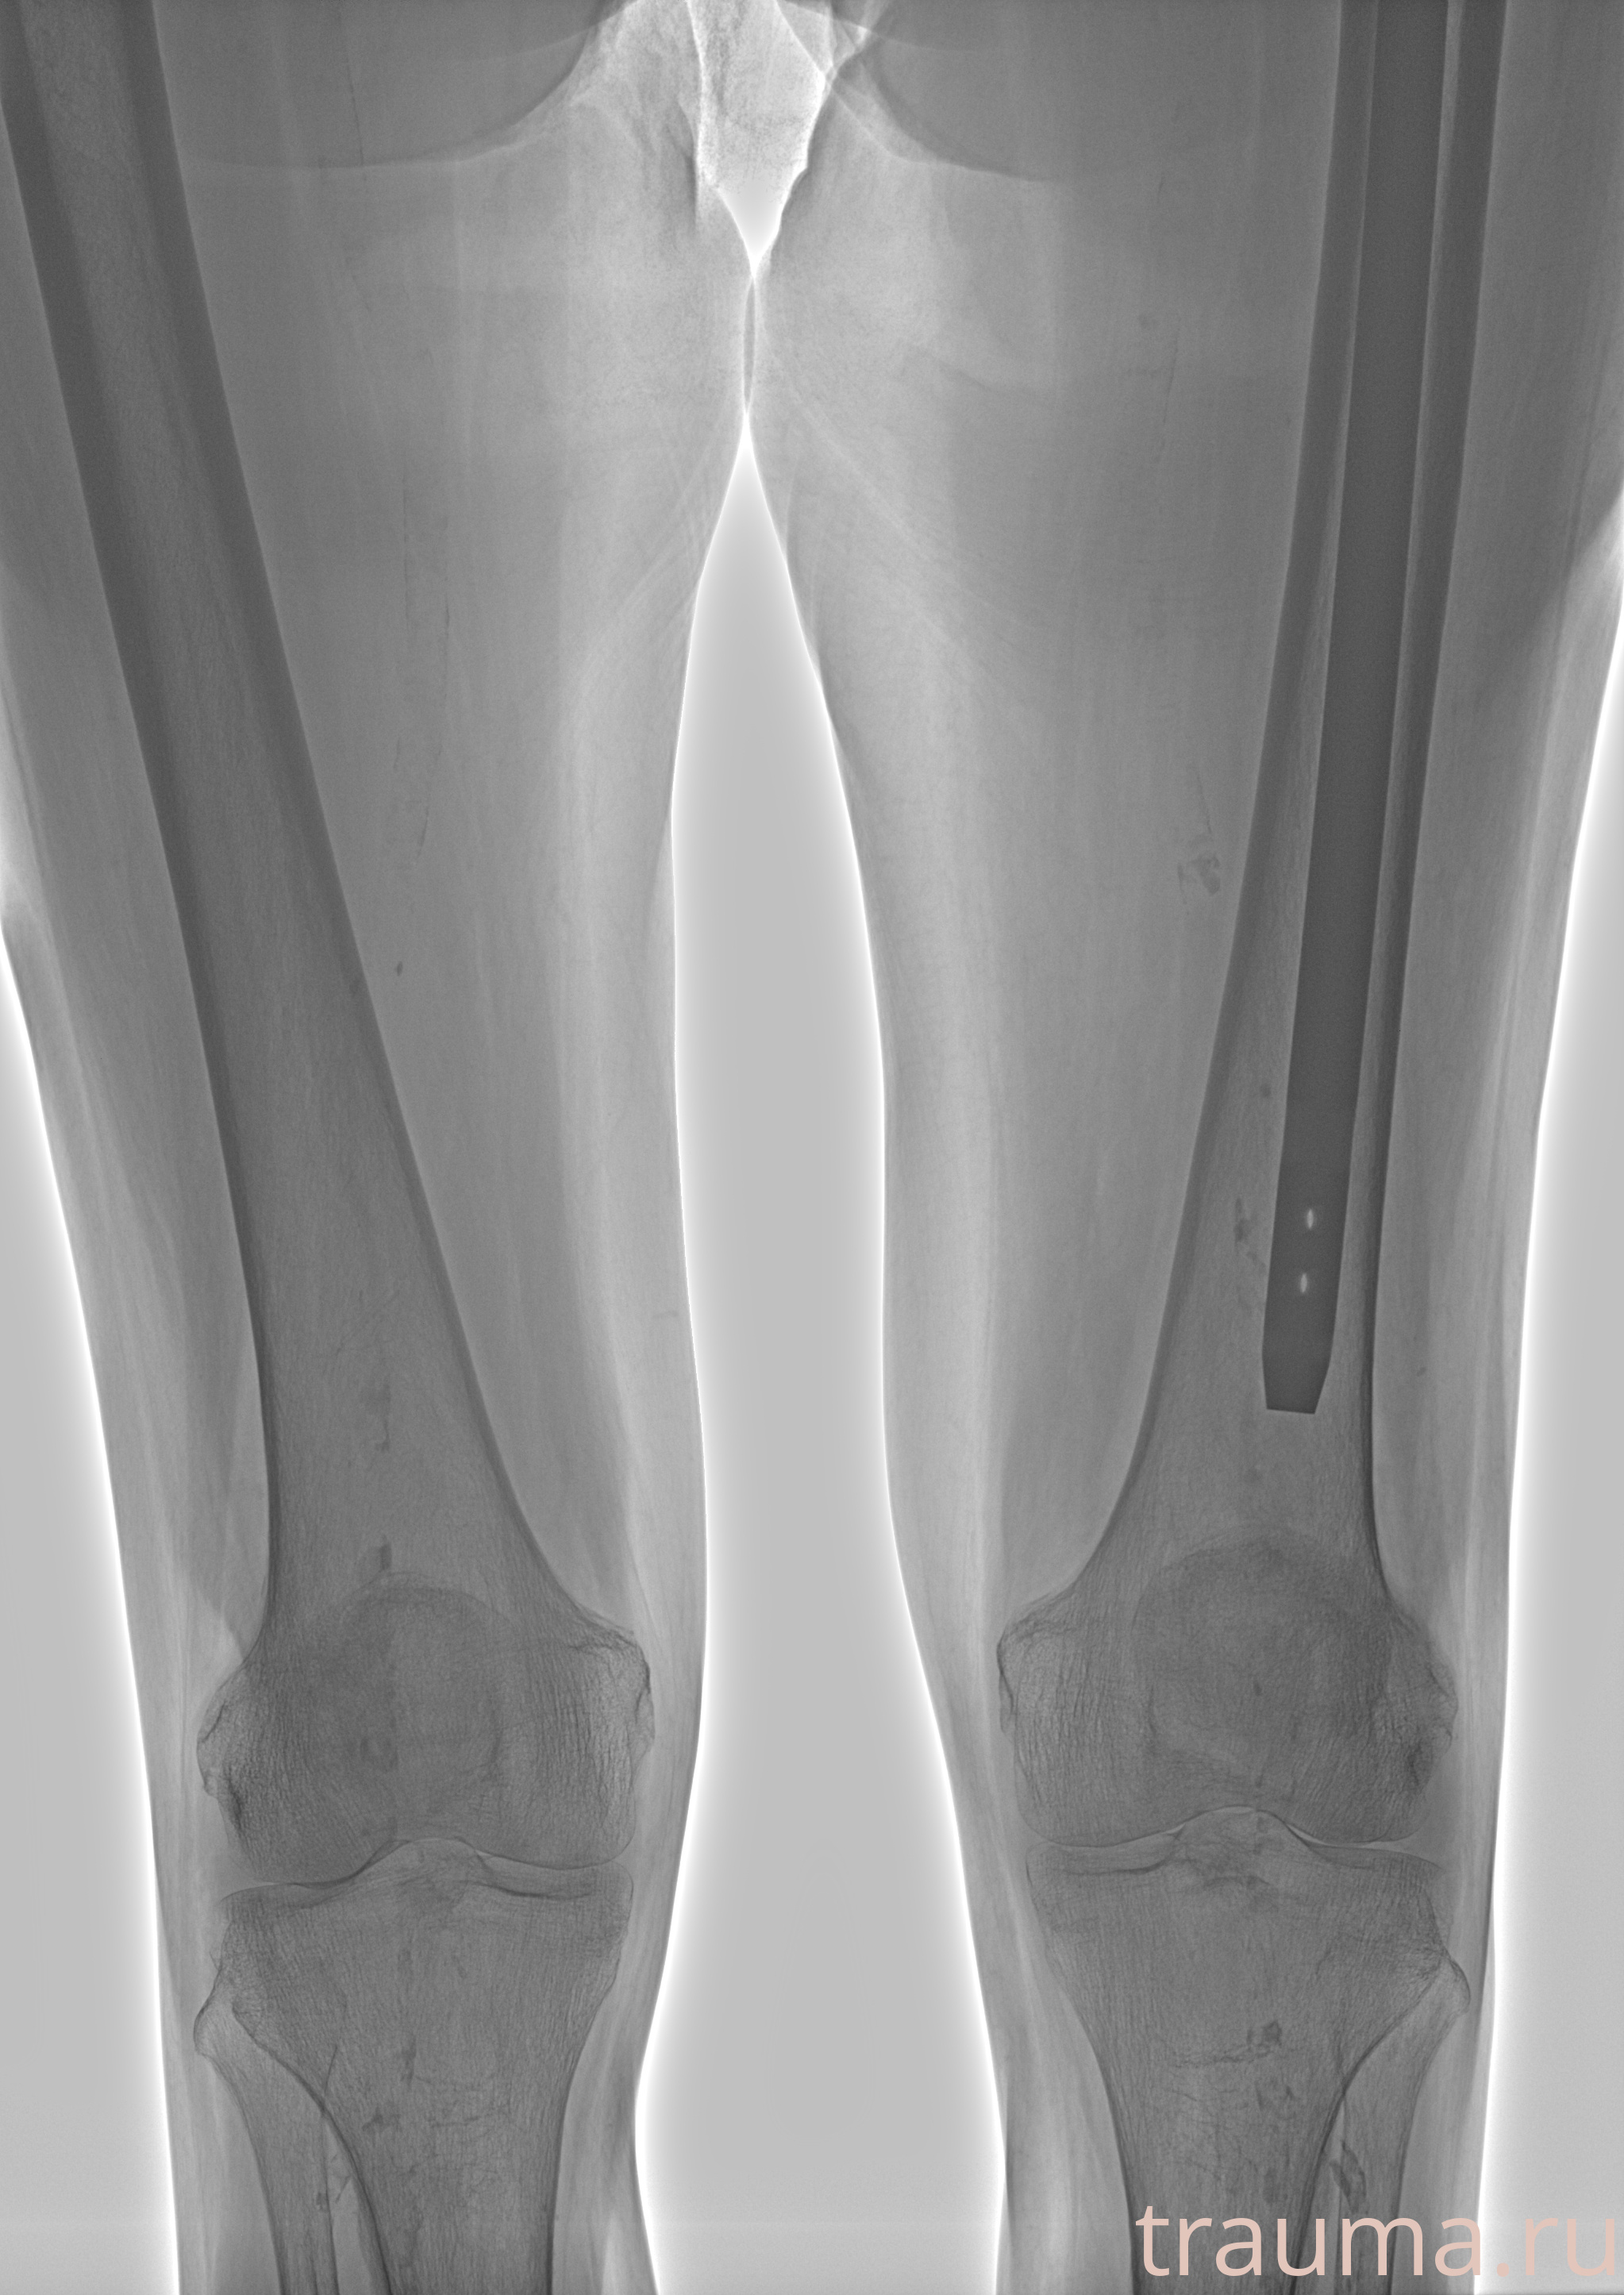

Рентгенограммы

Рентген на дому: по вашему адресу приезжает врач-рентгенолог, травматолог-ортопед с мобильным рентгеновским аппаратом, проводит диагностику травмы или заболевания, делает необходимые рентгенограммы, дает рекомендации по дальнейшему лечению. Получить качественные снимки в домашних условиях возможно благодаря уникальной методике, разработанной МосРентген Центром для института  Склифосовского